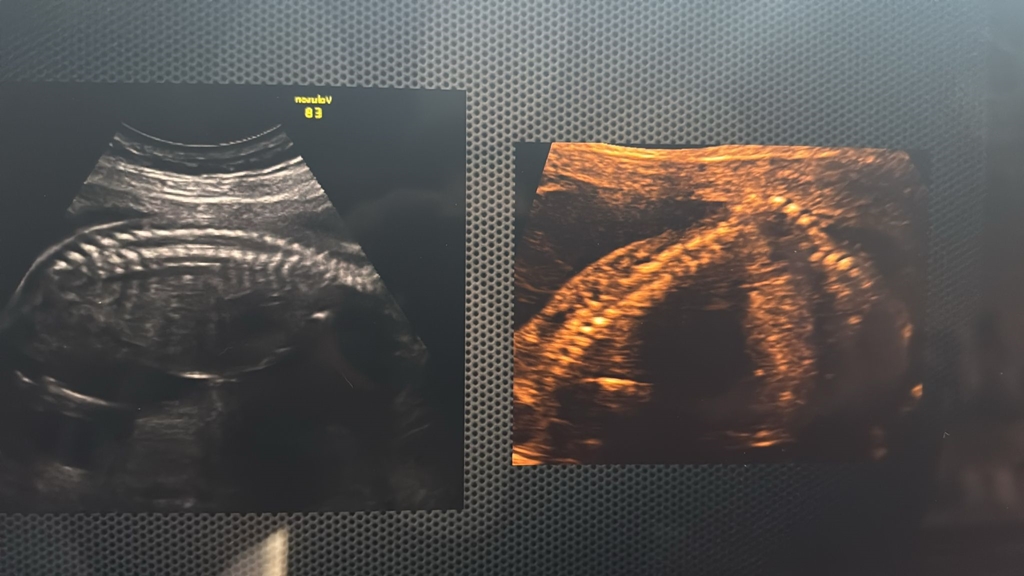

În mod normal, mamele ar trebui urmărite la șase săptămâni, să fie luate în evidență, să stabilim dacă este o sarcină cu risc obstetrical sau este o sarcină normală și de la prima luare în evidență să stabilim împreună cu pacienta o schemă de urmărire care să meargă până la final, până la momentul nașterii. Asta înseamnă, vorbim de o sarcină normală. Este luată in evidență, merge la medicul de familie, facem la 12 săptămâni screening-ul de primul trimestru, care înseamnă o eco-morfologie precoce, în care verificăm o parte din anomalii vizibile și facem screening-ul pentru anomalii cromozomiale, care este foarte important pentru că ecografic nu putem exclude anomaliile cromozomiale. Motiv pentru care este foarte important ca în primul trimestru să se facă acest screening.

După care este urmărirea lunară împreună cu medicul de familie, iar la 20 de săptămâni se face morfologia mare, cum spunem noi, de trimestru 2, unde teoretic putem să vedem 99% din anomalii.

Urmează iar ecografii lunare, analize de sânge lunare pe care le facem împreună cu medicul de familie, iar între 28-32 de săptămâni facem morfologia de trimestru 3, unde iarăși verificăm anomaliile structurale, poate găsim ceva ce am ratat din anumite motive în trimestrul 2 sau anomalii care apar doar în această perioadă, după care, după 32 de săptămîni, deja putem vedea cum a crescut copilul, cum stă copilul și putem să discutăm deja despre modalitate de naștere.